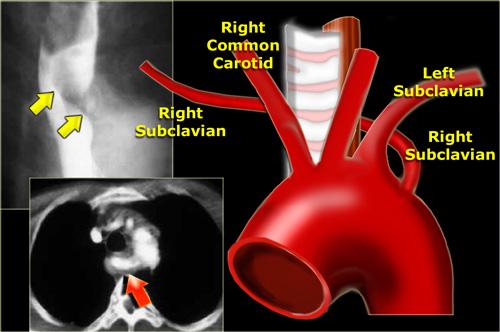

Động mạch dưới đòn phải bất thường

Đây là dị tật động mạch lồng ngực thường gặp nhất và hiếm khi gây triệu chứng.

Động mạch chạy lên trên và sang phải tạo ra ấn lõm chéo phía sau lưng trên thực quản (mũi tên).

CT cho thấy động mạch bất thường (mũi tên) là nhánh mạch cuối cùng xuất phát từ quai động mạch chủ và chạy phía sau khí quản và thực quản.